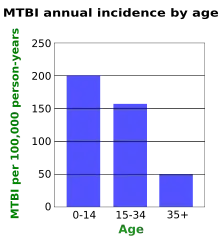

Age

Young children have the highest concussion rate among all age groups.[4] However, most people with a concussion are young adults.[119] A Canadian study found that the yearly incidence of mTBI is lower in older age groups (graph at right).[129] Studies suggest males develop mTBI at about twice the rate of their female counterparts.[3] However, female athletes may be at a higher risk of sustaining a concussion than their male counterparts.[130]